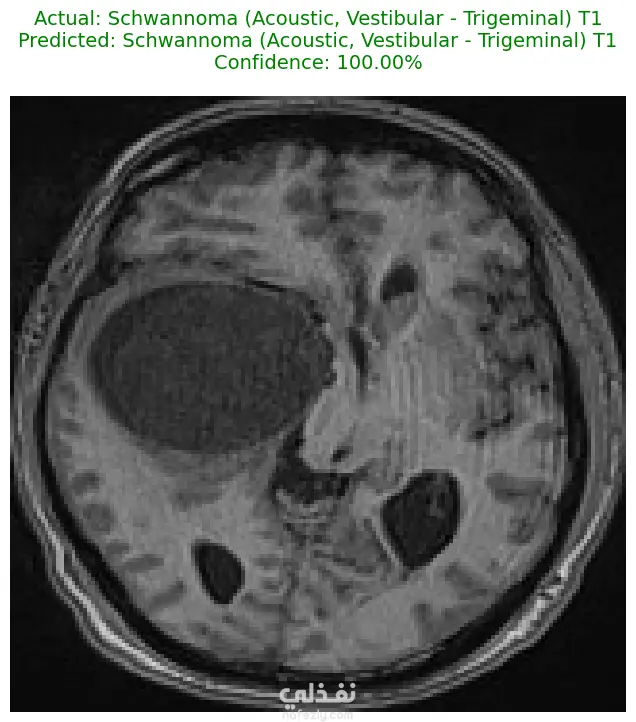

الوصف: قمت بتطوير نموذج تعلم عميق (CNN) قادر على التمييز بين 27 فئة مختلفة من الأورام والحالات الطبيعية بدقة تصل إلى 93%. شمل المشروع مراحل معالجة البيانات الضخمة، تنظيفها وموازنتها، وتصميم معمارية مخصصة لضمان الكفاءة العالية وتقليل استهلاك الذاكرة. المميزات التقنية: دقة استثنائية: حقق النموذج دقة تصل إلى 93% على بيانات التحقق (Validation Accuracy). معالجة البيانات الضخمة: تم العمل على قاعدة بيانات ضخمة، مع تطبيق استراتيجيات موازنة البيانات (Data Balancing) لضمان عدم انحياز الموديل. معمارية مخصصة: تم تصميم شبكة CNN تدعم تقنيات Batch Normalization لتسريع التعلم و Global Average Pooling لتقليل استهلاك الذاكرة وضمان استقرار النموذج. معالجة الصور: استخدام تقنيات OpenCV لقص الصور (Cropping) وإزالة الهوامش غير الضرورية لتركيز الموديل على منطقة الورم فقط. الأدوات والتقنيات المستخدمة: لغة البرمجة: Python. المكتبات الأساسية: TensorFlow / Keras. معالجة الصور: OpenCV & PIL. تحليل النتائج: Scikit-learn (Confusion Matrix & Classification Report). البيئة البرمجية: Google Colab (GPU Acceleration). النتائج المحققة: نموذج قادر على التعرف على أنواع نادرة من الأورام بدقة عالية. تقرير فني يوضح أداء الموديل لكل فئة (Precision & Recall). ملف نموذج جاهز للنشر (Deployment) بصيغة keras الحديثة. يمكنكم الاطلاع على الكود المصدري كاملاً والرسوم البيانية لتقييم أداء النموذج عبر رابط GitHub المرفق، كما يتوفر رابط تحميل النموذج المدرب داخل ملف الشرح.